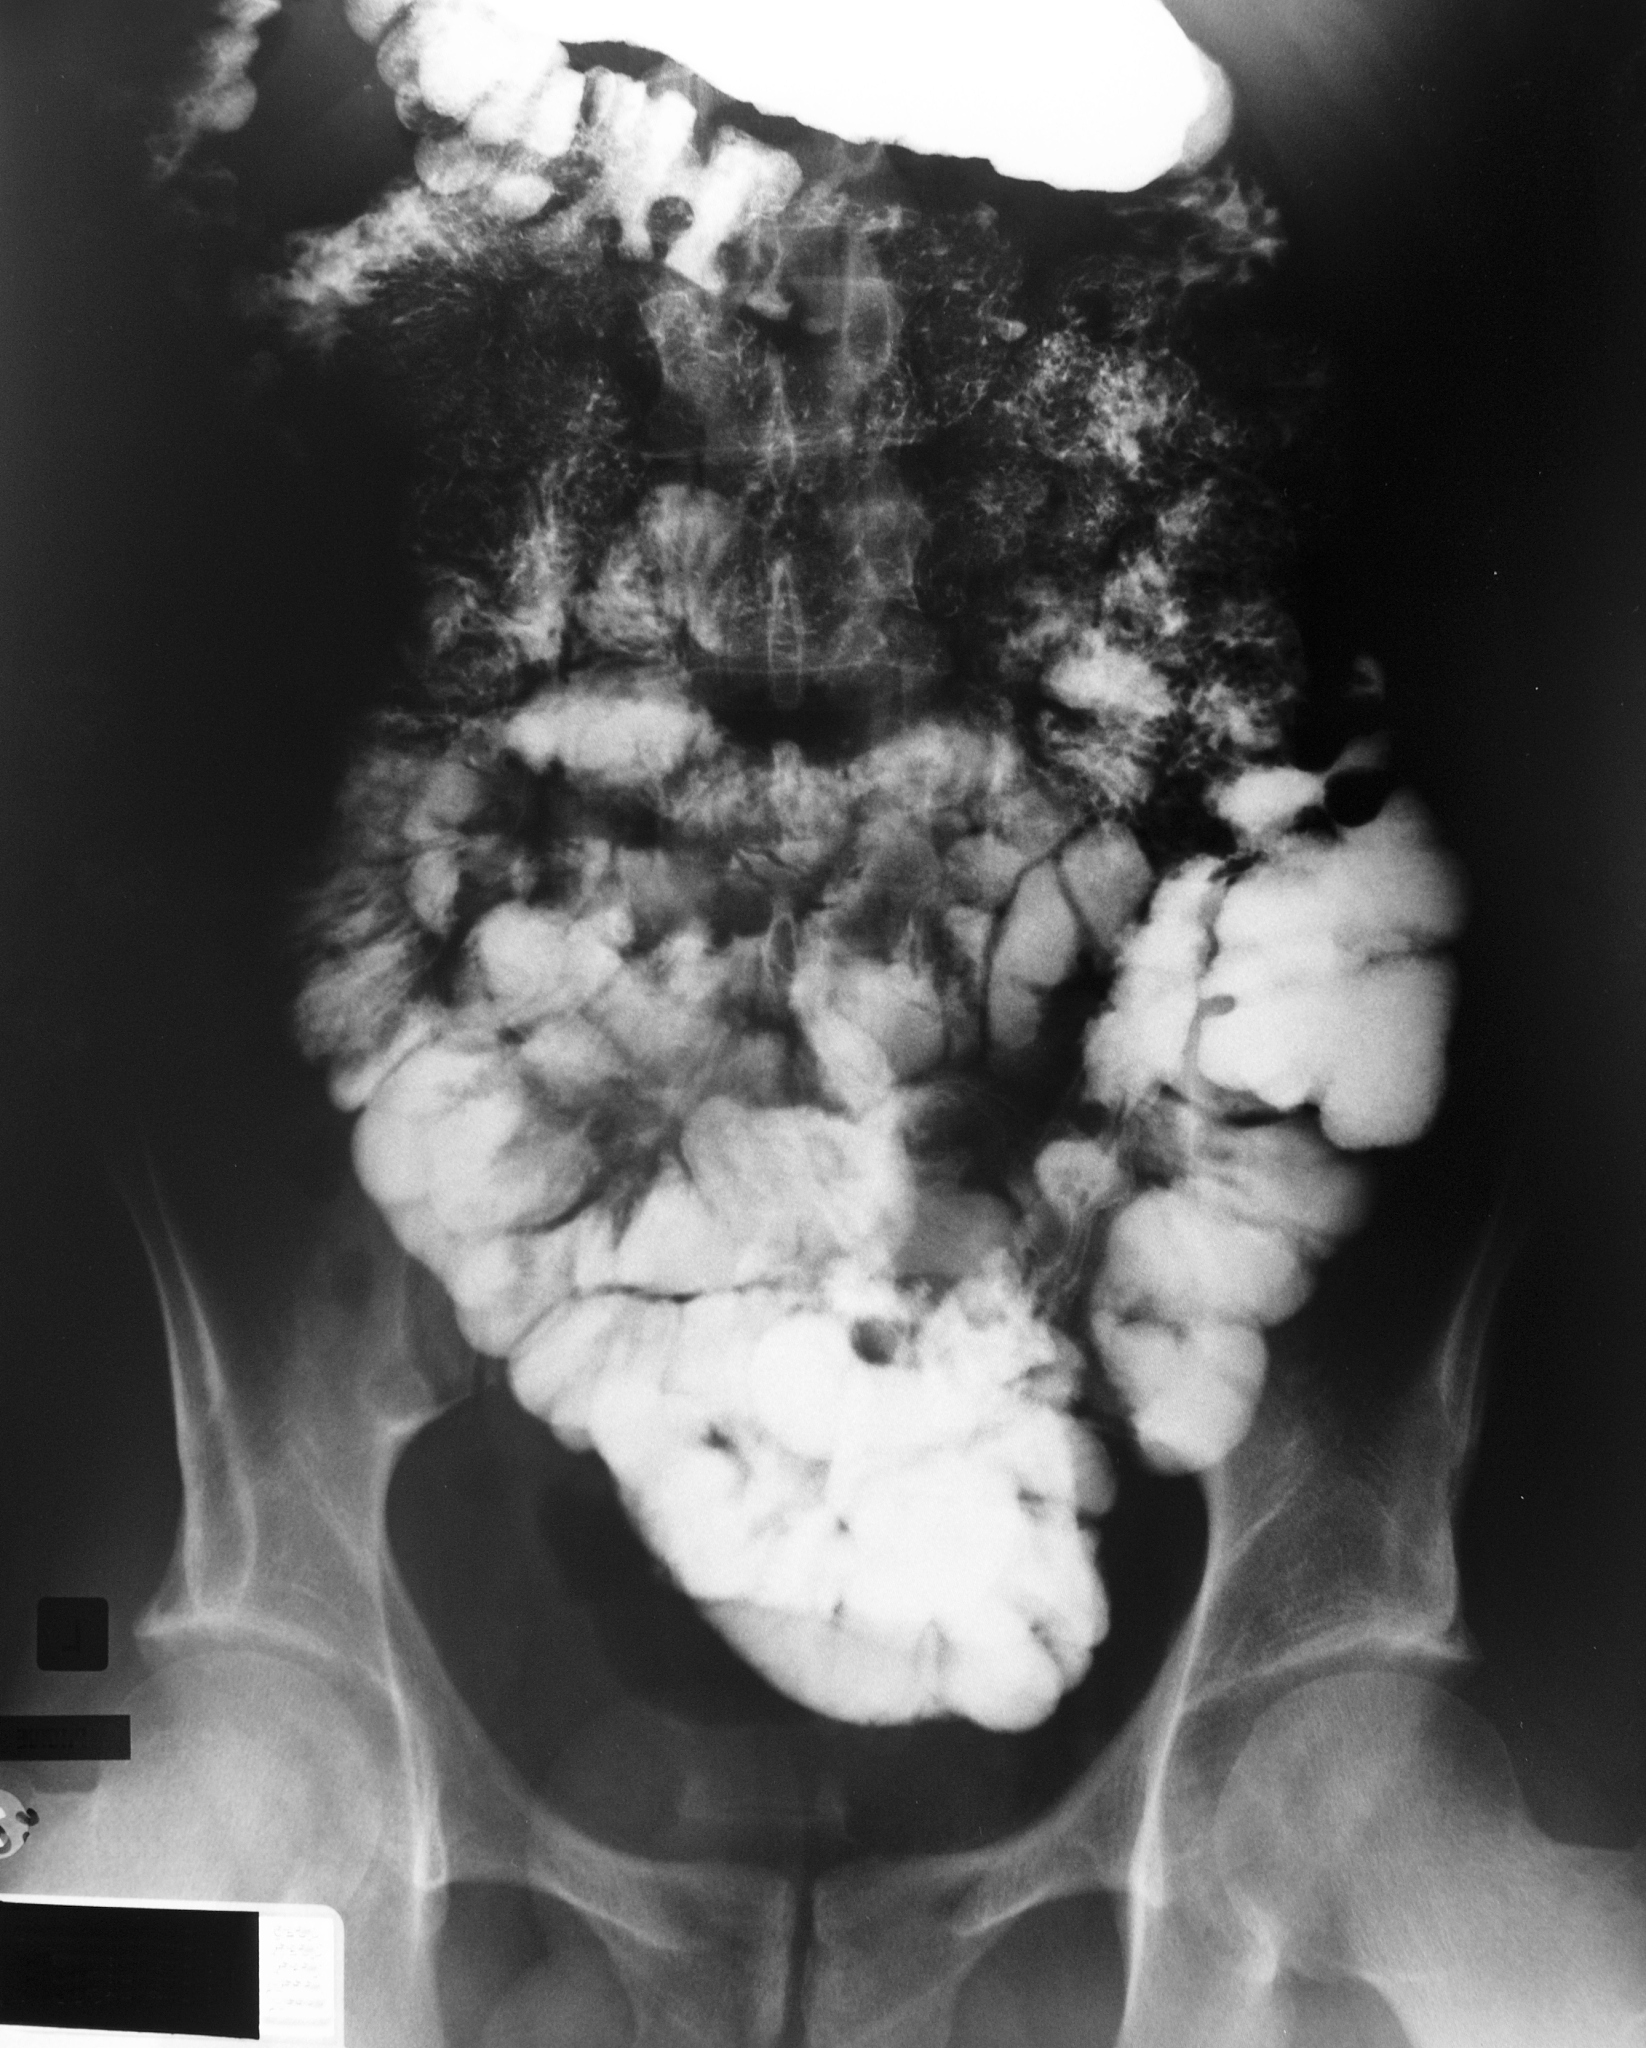

十二指肠溃疡可以是一种严重的疾病,如果不及时治疗,可能会导致严重的并发症,如出血、穿孔和梗阻等,甚至危及生命。因此,如果怀疑自己患有十二指肠溃疡,应及时就医,接受专业的诊断和治疗。